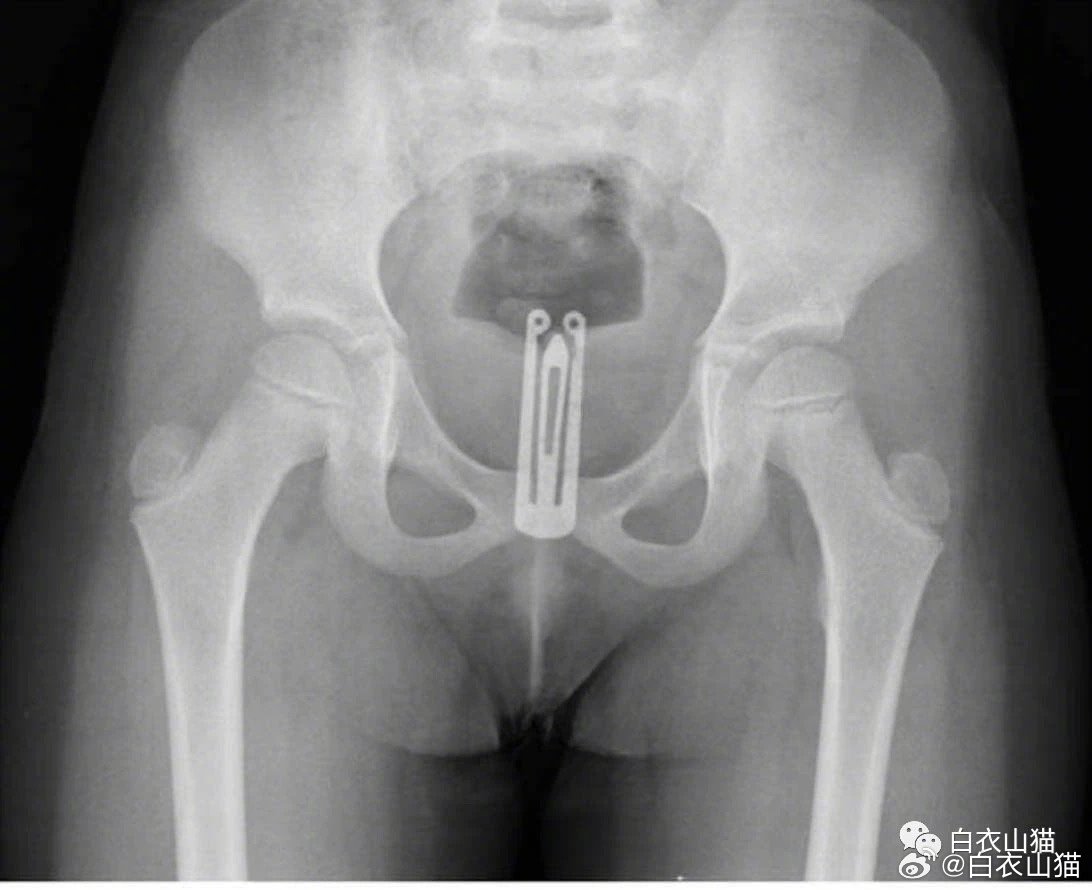

图片5

5岁女童阴道内的纽扣电池。

图片6

5岁女童阴道内的发夹。